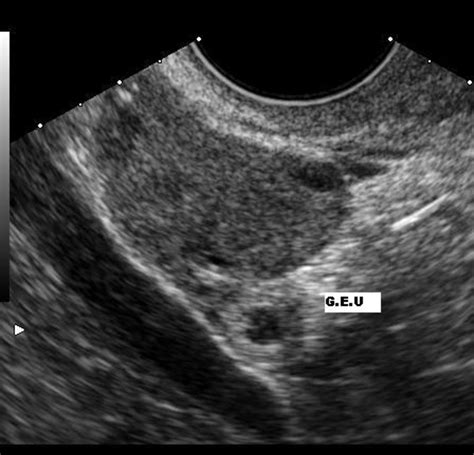

When doctors look for an ectopic pregnancy by ultrasound, they are essentially looking for an "empty" uterus where there should be a pregnancy sac. The diagnostic process typically involves:

• Locating Adnexal Masses: A mass outside the uterus in the adnexal region (where the fallopian tubes and ovaries are located) often suggests an ectopic implantation.

• Checking for Free Fluid: The presence of free fluid in the pelvic cavity, especially in the pouch of Douglas, can indicate internal bleeding caused by a rupture.

Adnexal Mass Often represents the ectopic gestational sac or a blood clot.

Free Pelvic Fluid A critical warning sign of potential tubal rupture or hemorrhage.